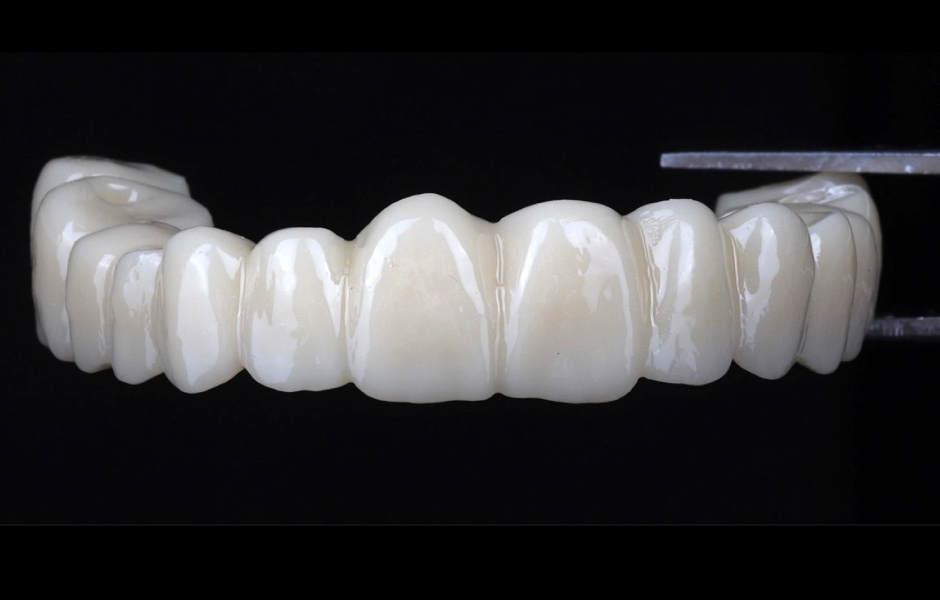

Pro kotvení definitivní náhrady byly použity abutmenty Variobase® for Bridge. Materiálem pro výrobu definitivní náhrady byl zvolen monolitický zirkon (obr. 49, 50).

Definitivní náhrada byla nasazena a ověřena z hlediska estetiky, okluze a funkce (obr. 51–55). Panoramatický kontrolní snímek potvrdil, že všechny parametry protetického ošetření odpovídají očekávaným hodnotám (obr. 56).

Obr. 49

Obr. 50